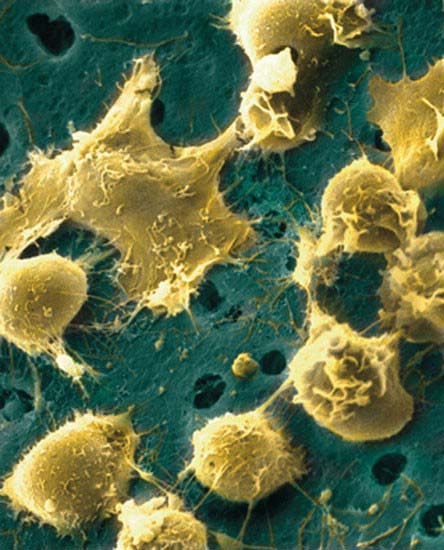

سلول های سرطانی سینه